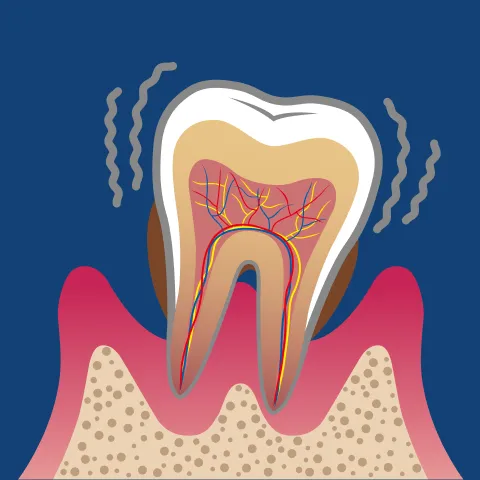

そして「重度歯周炎」に進行すると、歯槽骨の大部分が溶け、歯が支えを失ってグラグラの状態に。

歯ぐきから膿が出たり、強い口臭を伴ったりすることも多く、最終的には歯が自然に抜け落ちてしまうこともあります。ここまで進行すると、失われた骨や歯周組織を再生させる「歯周組織再生療法」など、より高度な治療が必要となります。

歯を支える骨(歯槽骨)が溶け、

最終的に歯が抜け落ちる

歯をしっかりと支えているのは、目に見えない部分にある「歯槽骨」という骨です。

歯周病が進行すると、歯周病菌が放出する毒素や炎症性物質がこの骨にまで影響を与え、少しずつ吸収・破壊していきます。骨が減少するにつれて歯の根が露出し、支えを失った歯は動きやすくなります。患者さんの中には「歯が浮いたような感じがする」「前歯のすき間が広がってきた」といった変化を感じる方も少なくありません。

歯槽骨が溶けていくスピードには個人差がありますが、数年単位で進行することが多いです。

放置すれば、炎症がさらに広がり、最終的に歯が自然に抜け落ちてしまうこともあります。実際、日本人が歯を失う原因の第1位はむし歯ではなく歯周病です。